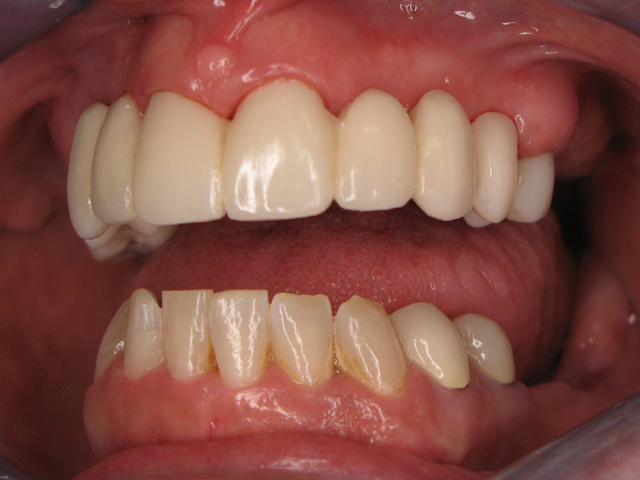

Here is the finished case before sending it back to the dentist (Figs. 23-25) and here is the final seated case (Figs. 26-28).

Fig. 25                                                                   Fig. 26

As you can see from the picture, the patient was extremely happy with her permanent smile and so was the doctor.